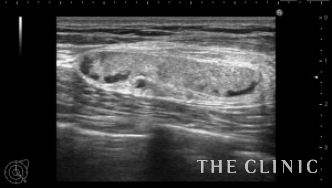

左胸に4㎝弱のしこりが触れ、エコーでは充実性のしこりでした。

壊死した脂肪が液状化したオイルシストであれば、注射針で吸引除去することが可能ですが、充実性の場合は吸引することは難しいです。